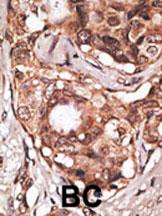

IHC (Immunohistochemistry)

(The image on the left is immunohistochemistry of paraffin-embedded Human thyroid cancer tissue using AAA241069(EIF4G1 Antibody) at dilution 1/30, on the right is treated with synthetic peptide. (Original magnification: ×200))